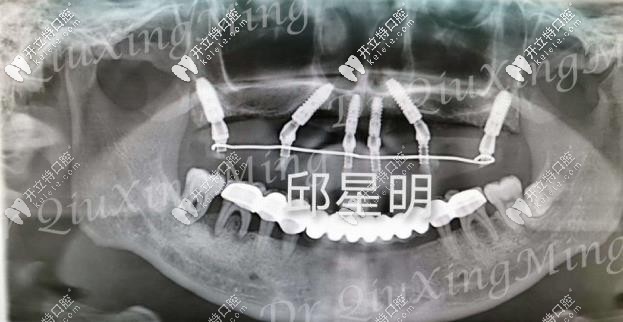

植入種植體的牙片

種植過程也挺快的,大約用了兩個多小時,六根植體就已經(jīng)植入進去了,然后需要等2-3個月的牙床恢復(fù)期,才能安裝基臺和牙冠。這段時間只需安心等待就好了!